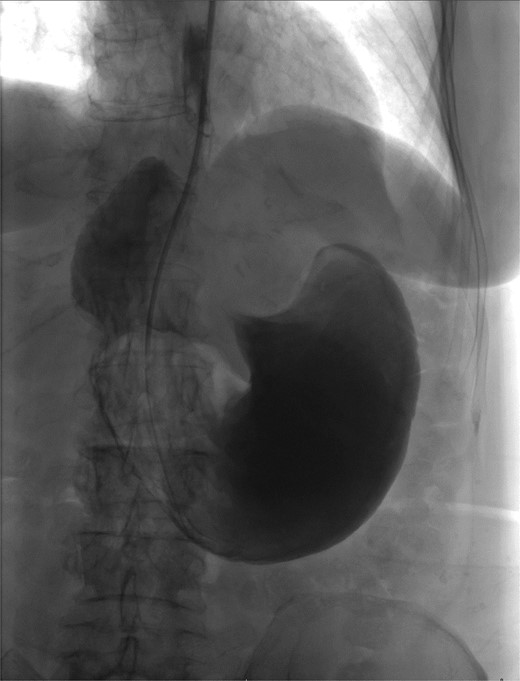

The patient was a 74-year-old female with a history of hypertension, chronic migraines, hiatal hernia repair with Nissen fundoplication repair, and cecal volvulus treated with right hemicolectomy who presented with abdominal pain, nausea, and vomiting. Six months prior, she exhibited symptoms of bloating and nausea, which were treated with oral Reglan with some improvement. She reported vomiting episodes for 2 months that acutely worsened over the 4 days prior to presentation. Examination revealed a soft and mildly distended abdomen with tenderness in the epigastrium and left upper quadrant. Initial vital signs showed a temperature of 36.1°C, blood pressure of 149/88 mmHg, heart rate of 115 beats/min, and oxygen saturation of 95% on room air; tachycardia resolved with resuscitation. Labs were notable for a white blood cell count of 8.8 × 1000/mcL and hemoglobin of 14.2 g/dL. Sodium was 137 mEq/L, potassium was 3.3 mEq/L, and creatinine was 0.75 mg/dL. Computed tomography (CT) of the abdomen and pelvis (Figs 1 and 2) showed gastric volvulus without pneumatosis, significant wall thickening, or distention. Nasogastric tube was placed. An upper gastrointestinal fluoroscopy scan showed no passage of contrast beyond the stomach and demonstrated 90° rotation of the stomach (see Fig. 3). The patient underwent surgery that same day.

Upper GI study demonstrating no passage of contrast beyond stomach and 90° rotation.